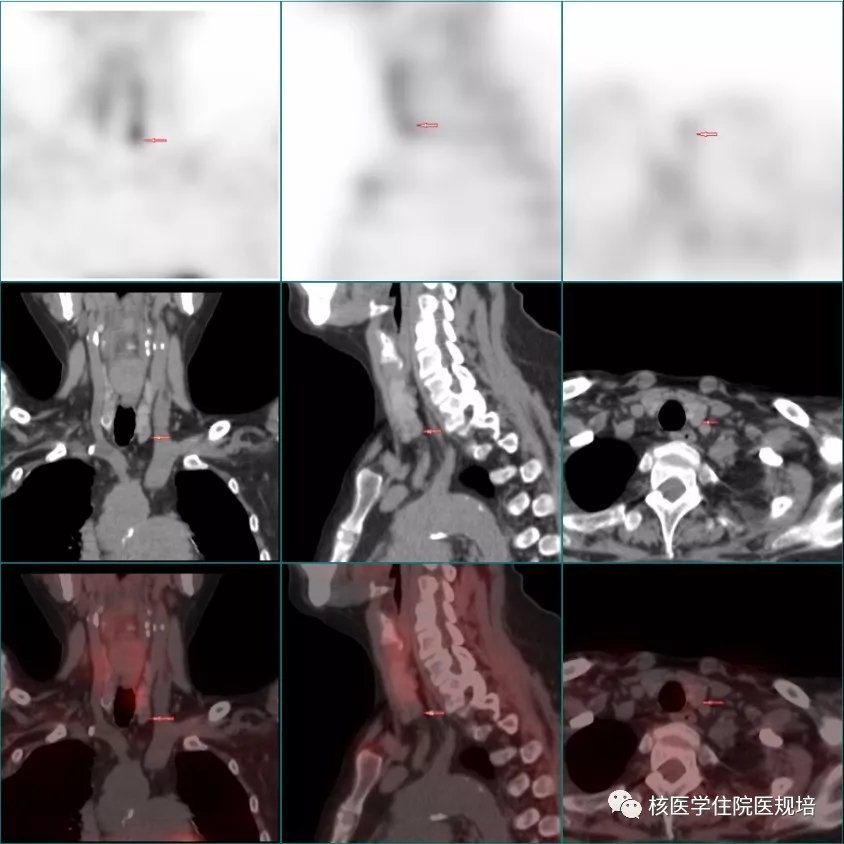

图1

静脉注射99mTc-MIBI后,分别于15min和2h行颈部-上胸部静态平面显像。结果显示:早期显像可见双叶甲状腺显影基本清晰,放射性分布不均匀,左叶下极可见一点状放射性浓聚灶;延迟显像中叶甲状腺影像明显减淡,前述浓聚灶仍隐约可见。之后行上述区域SPECT/CT显像,结果显示,平面像所示左叶甲状腺下极放射性浓聚灶位于左叶甲状腺下极下方气管旁,相应部位CT见一范围约1.6×1.0×1.1cm的低密度结节影,边界清晰,与邻近甲状腺组织分界明显;另于CT影像上发现左叶甲状腺上极背侧及右叶中部背侧各有一稍低密度小结节影,范围分别为0.8×0.7×0.4和1.3×1.0×0.5cm,均未见明显放射浓聚。此外,SPECT/CT成像野内见骨骼弥漫性轻度放射性摄取,相应部位CT骨质形态及密度均未见明显异常;双肩关节周围可见不规则结节样团块状高密度影,范围分别为7.8×7.3×6.6cm和6.2×5.5×3.4cm,均未见明显放射性浓聚。

左叶甲状腺下极MIBI摄取增高灶,考虑为功能亢进的甲状旁腺,增生腺体可能性大。

左叶甲状腺上极背侧及右叶甲状腺中部背侧小结节,未见明显MIBI摄取,但不除外甲状旁腺增生可能。